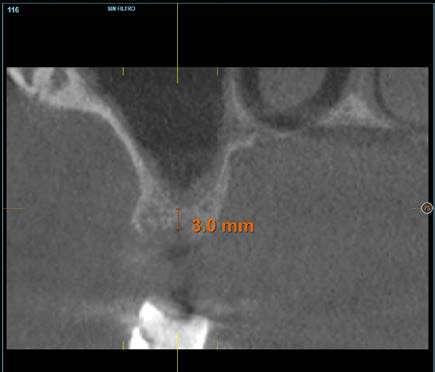

Figuras 3 y 4 . Corte del Cone-beam dental tras la exodoncia y regeneración del alveolo con Endoret-PRGF cuatro semanas después. Podemos observar la atrofia ósea en sentido vertical de la zona con una altura máxima de 3 mm. La planificación como podemos visualizar será para la realización de una elevación transcrestal mínima y la colocación de un implante extracorto.

Figura 12. Mantenimiento de la altura ósea lograda y de la estabilidad del implante al año de carga visualizada en cone-beam.